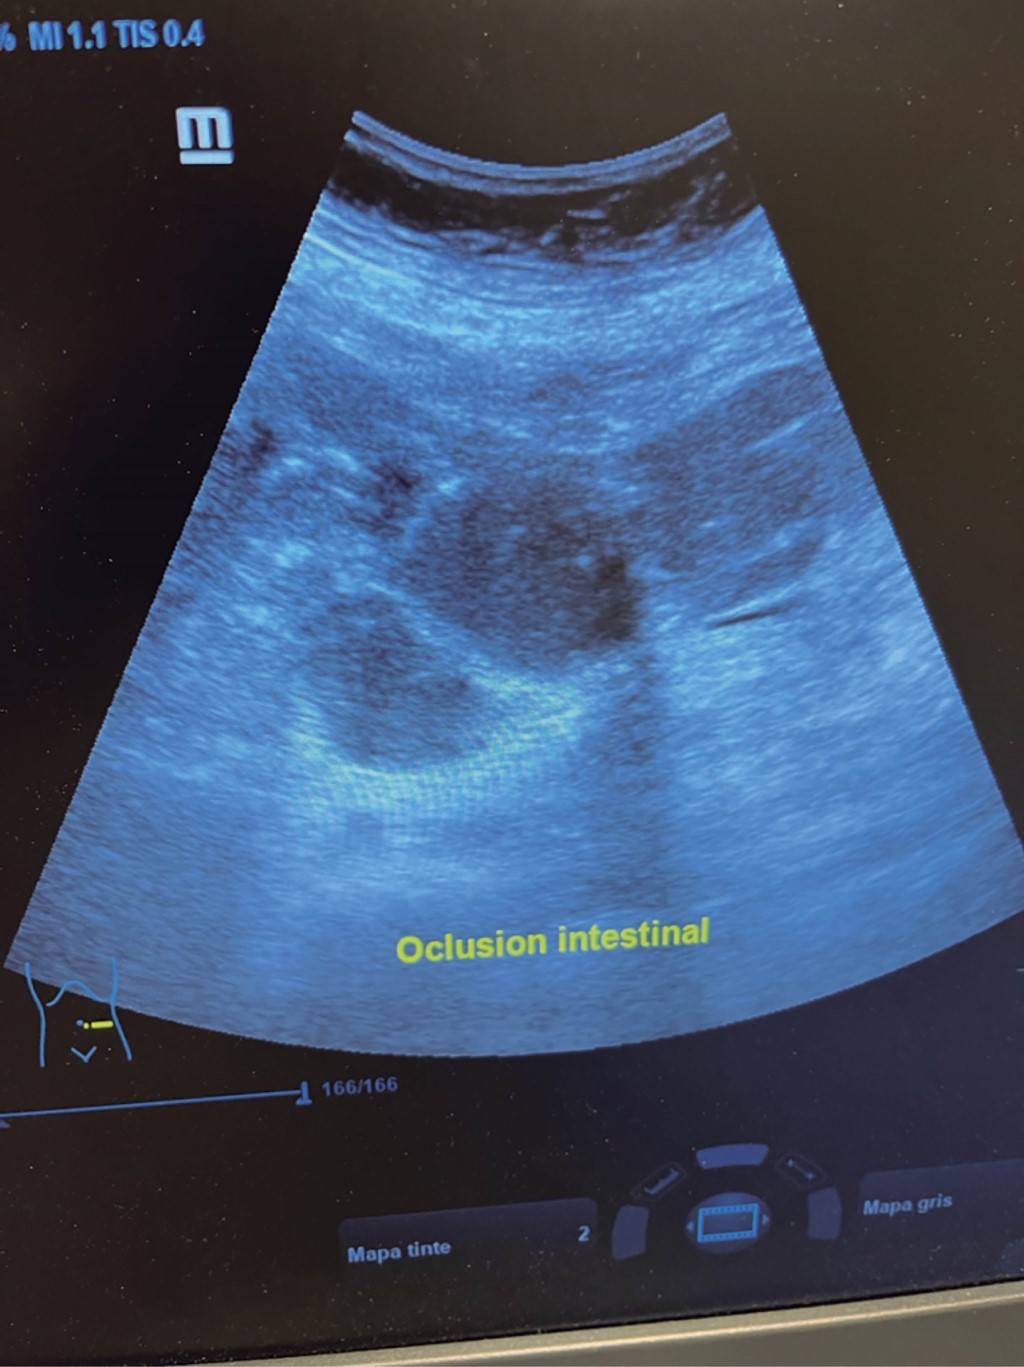

El cirujano general aborda particularmente problemas clínicos que incluyen el aparato digestivo, el cuello, la pared abdominal y los trastornos del sistema circulatorio y el tórax. Un artículo publicado en 2008, por Lindelius,15 demostró que la implementación del ultrasonido por parte del cirujano general en casos de dolor abdominal agudo incrementó en 7.9% la precisión diagnóstica. En la consulta cotidiana de la especialidad, incorporar el rastreo sonográfico al área explorada agrega minutos al examen clínico que aportan datos de notable valor por la objetividad y precisión. El abdomen suele ser el sitio que los cirujanos generales exploramos con más frecuencia. Es posible en una consulta cotidiana hacer todo el protocolo de ultrasonido de abdomen superior en minutos, que incluye ambos cuadrantes superiores y los flancos, pudiendo observar el hígado, la vesícula y los conductos biliares, ambos riñones, el bazo, parte del páncreas y, con ayuda del Doppler color, los principales vasos de la región como la vena cava inferior, la aorta abdominal, la vena porta, los vasos esplénicos y la arteria hepática. Puede haber limitantes como el contenido gástrico, el nivel de llenado de la vesícula biliar o la constitución del paciente y su capacidad de cooperar con el estudio. Pero con la práctica cotidiana, se adquieren las destrezas y el refinamiento suficientes para lograr, con la experiencia acumulada, producir imágenes de relevancia diagnostica inmediata. En la fase de entrenamiento, contrastar nuestros hallazgos con información disponible en la red, con los colegas imagenólogos, o cirujanos ya experimentados en ecografía, permitirá la retroalimentación y la tutoría esenciales de toda curva de aprendizaje. Tradicionalmente se consideraba que aquellos órganos que contienen una mezcla de líquido y gas (intestino, estómago) no son valorables por ultrasonido, el gas produce un efecto rarefacción, ya que no comprime las ondas como un tejido solido o un medio líquido, la señales entonces se dispersan impidiendo que regresen como ecos y permitan al procesador formar una imagen congruente con el órgano explorado. Sin embargo, cuando esta condición cambia como consecuencia de un estado patológico, es posible identificar el contenido intestinal o el gástrico y darnos una idea más aproximada de lo que realmente está ocurriendo en ese abdomen. Podemos, por ejemplo, saber si un estómago está lleno de líquido, o si el intestino contiene residuo sólido, líquido o gaseoso. Los equipos actuales pueden incluso ver en detalle la pared intestinal cuando ésta esté dilatada. Se puede distinguir cuando el colon está ocupado de líquido a nivel del flanco izquierdo como podría ser en una colitis amebiana o en una oclusión intestinal,16 donde se observa dilatación del intestino delgado ≥ 25 mm, el peristaltismo anormal, la presencia de líquido libre intraperitoneal y el edema de la pared intestinal (Figura 2). En casos de dolor abdominal agudo, el ultrasonido puede, en forma inmediata, permitir diagnósticos diferenciales como el hallazgo de una dilatación pielocalicial por nefrolitiasis (Figura 3), o un aneurisma de la aorta abdominal (Figura 4). Un estudio prospectivo realizado en Irvine, California,17 encontró que la a capacidad diagnóstica del médico de primer contacto practicando el ultrasonido para detectar una colelitiasis tiene una especificidad de 87% y una sensibilidad de 82%, mientras que la prueba de ultrasonografía realizada por radiología tuvo sensibilidad de 83% y una especificidad de 86%. Es decir, que, ahorrando tiempo al paciente, el diagnóstico de colelitiasis es factible agregando unos minutos al examen físico inicial. En casos de apendicitis, el método diagnostico considerado como el estándar de oro es la tomografía axial computarizada (TAC). Sin embargo, tiene inconvenientes como su disponibilidad, su costo, el riesgo de radiación en niños y pacientes embarazadas. En tales situaciones, sobre todo en niños, sexo femenino o pacientes delgados, el ultrasonido es una poderosa herramienta que complementa el examen clínico inicial. Las ventajas del ultrasonido frente a la tomografía serian su ubicuidad (ya está en la sala de emergencias), el bajo costo, la ausencia de radiación y el diagnóstico diferencial con causas ginecológicas o genitourinarias de dolor. En apendicitis, la sensibilidad y especificidad de la TAC es de 99.4% y 80.0%, respectivamente. Para el ultrasonido, la sensibilidad diagnóstica es de 83% y la especificidad de 90%. La tasa de apendicectomía negativa es ligeramente mayor en el grupo de TAC que en el del ultrasonido, es decir, 7.1% (3/42) (TAC) en comparación con 4.67% (5/107) (ultrasonido). Hay que recalcar que el ultrasonido es operador dependiente. La experiencia y la calidad del equipo juegan un papel importante.18 La apendicitis tiene varios hallazgos característicos, como la pared edematosa y el aumento de grosor general. Se toman para criterios de positividad una estructura tubular aperistáltica no compresible que mide más de 6 mm de diámetro en el cuadrante inferior derecho (Figura 5).19-21

Figura 2